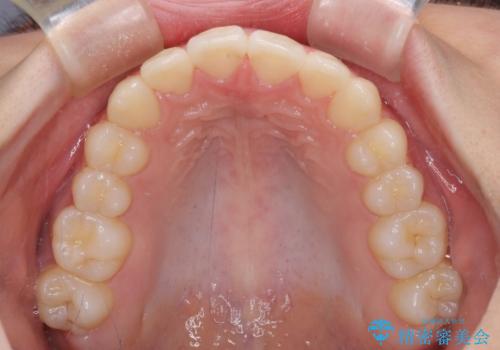

- 口元のデコボコを気にして来院された患者様です。

前歯の捻れにより口元が閉じにくくなっていたため、歯列全体の側方への拡大と、歯と歯の間を少し削ってスペースを獲得することとしました。

ゴムかけをしっかりと行ってもらい、スッキリとした口元に仕上げることができました。